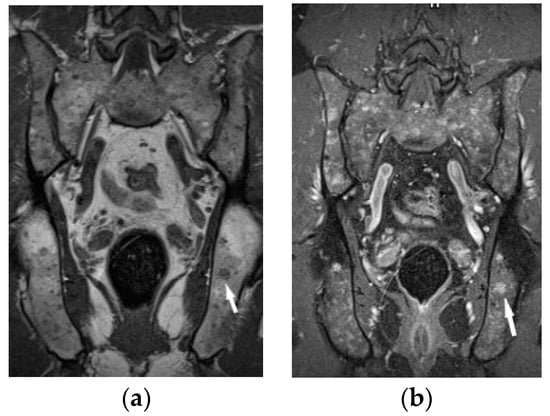

The lumbar spine MRI revealed protrusion of an intervertebral disc with compression on the dural sac and nerve roots, which presumably caused the symptoms. Moreover, the images of lumbar vertebrae and pelvis showed disseminated, small enhancing lesions (Figure 11a,b), which were isointense on T1- and T2-weighted images, hyperintense on TIRM images and revealed restricted water diffusion. The MRI appearance of the lesions was nonspecific. However, the radiologist interpreting the results had access to clinical data so the differential diagnosis took into account both sarcoidosis and metastases.

It was decided to repeat bronchoscopy. Pathological confirmation of sarcoidosis was obtained from a biopsy of the bronchial mucosa (non-necrotizing granulomas and multinucleated giant cells). To exclude other than sarcoidosis changes in the bones and bone marrow, the patient was consulted in hematology and orthopedic medical centers. Iliac bone biopsy revealed multinucleated giant cells and epithelioid granulomas without necrosis. In bone fragment-containing bone marrow, the image was suggestive of sarcoid granulomas as well. Due to confirmation of sarcoidosis with bone and bone marrow involvement and progression of lung disease, prednisone at a dose of 30 mg per day and methotrexate at a dose of 20 mg per week was implemented. As a result of treatment, almost complete regression of lung disease in the control chest CT, and normalization of respiratory parameters, was observed. Normalization of calcium level in 24-h urine test (Table 1), and regression of enlarged lymphatic abdominal nodes were also noted. Control MR imaging showed almost complete regression of intramedullary foci in lumbar vertebrae and complete regression of intramedullary foci in the pelvic bone elements (Figure 11c,d). Therefore, the dose of prednisone was gradually reduced to 10 mg per day and methotrexate to 10 mg per week.

Figure 11. 34-year-old patient. T1-weighted images, contrast enhanced, with fat saturation of the lumbar spine and pelvis. Multiple enhanced bone marrow lesions in the vertebral bodies ((a), white arrow) and in the pelvis at the level of the sacroiliac joints ((b), white arrow). Complete regression of the lesions after the treatment in the vertebral bodies (c) and pelvis (d).